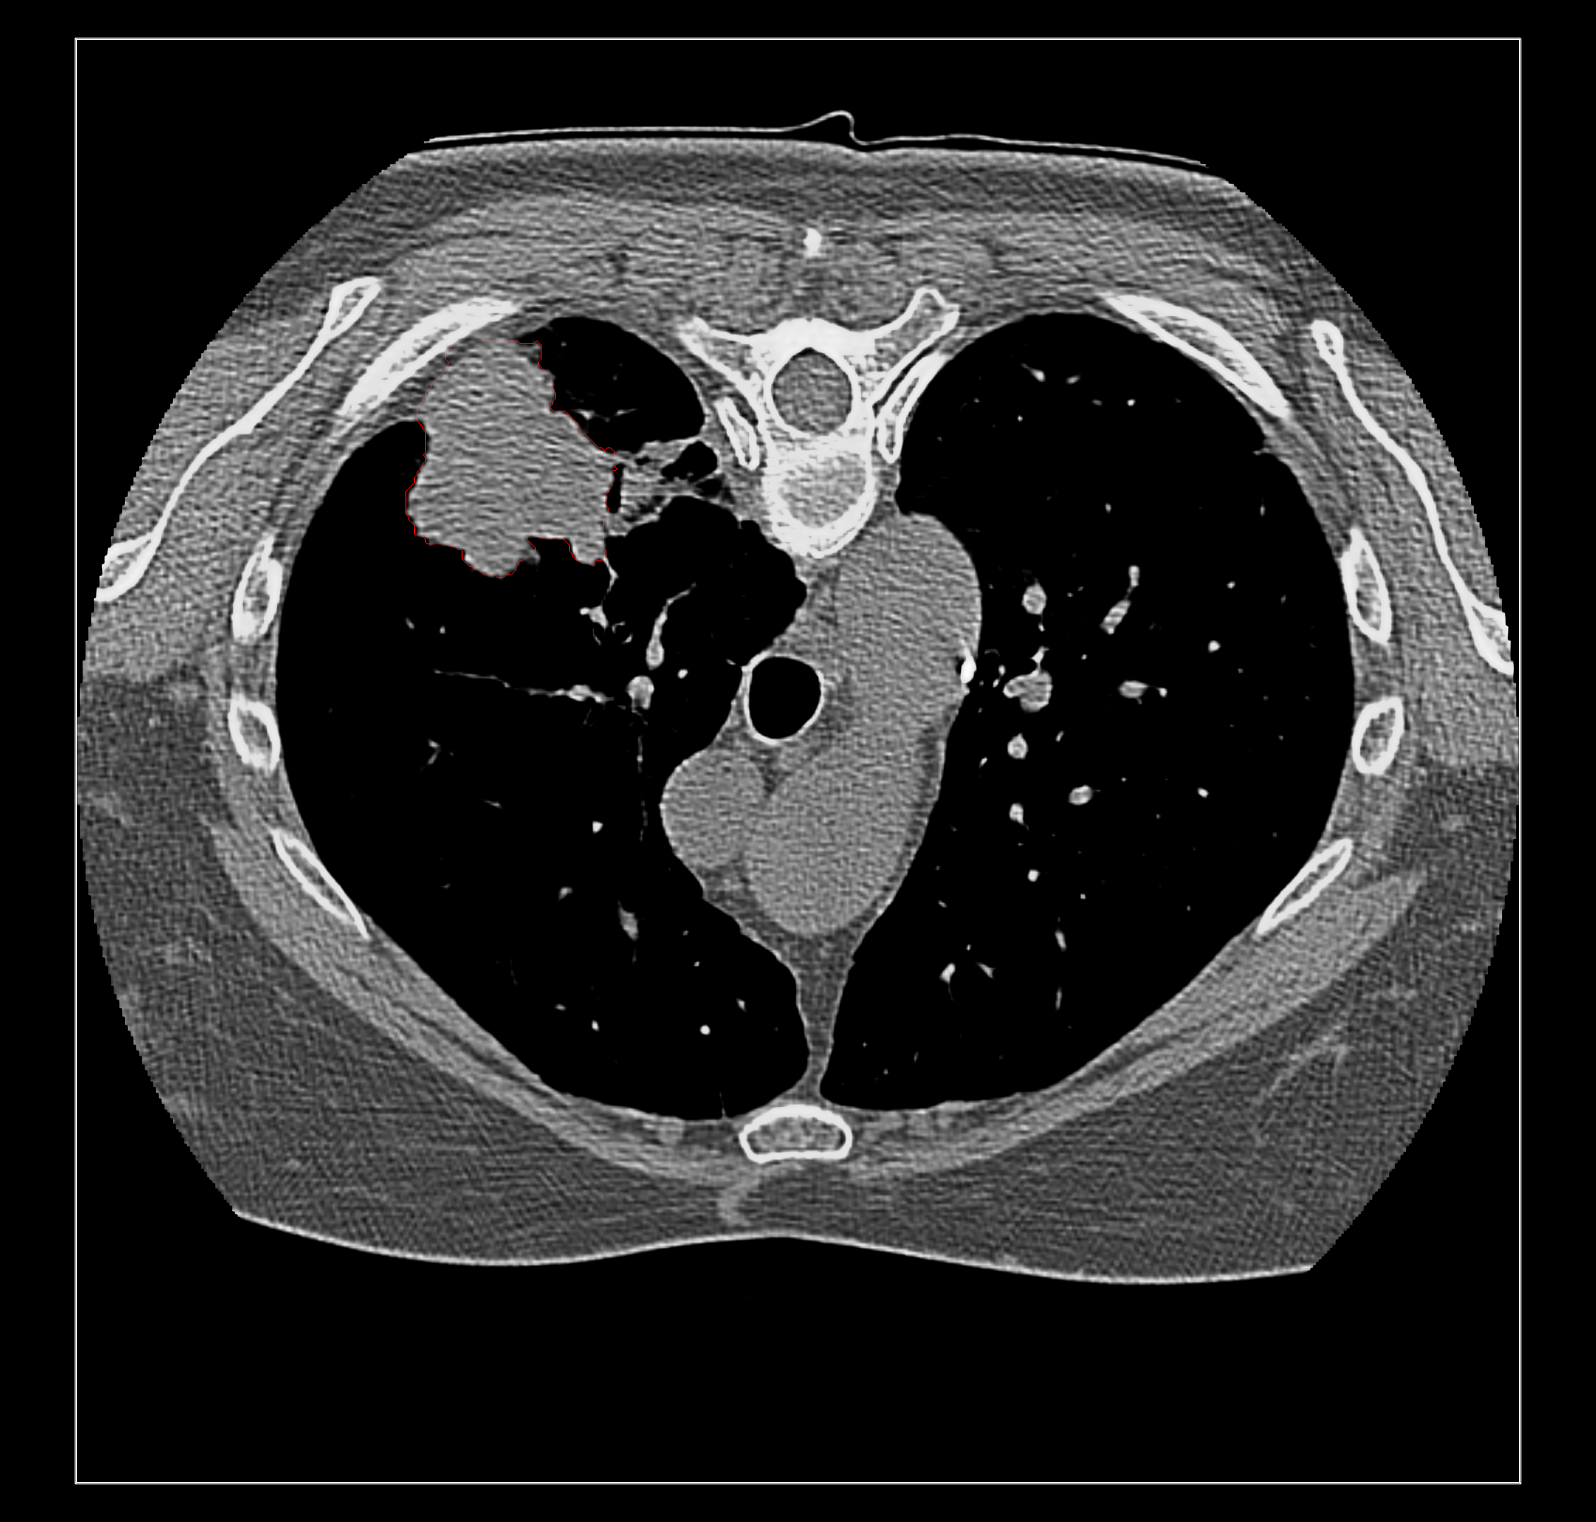

Surface rendering of segmentation channels avoids this problem. But I suspect coloring the image data according to the segmentation is far more useful to researchers looking at medical imaging because unlike a surface it allows you to see the intensities in the segmented region. For instance that helps you judge if the segmentation is correct. Sometimes a surface is best, for instance if you just want to see the size of a segmented tumor or compare the size a month ago to now using transparent surfaces can do that. I guess my overall assessment is that good quality medical imaging visualization needs the fancier blending. Because medical imaging is significantly different from electron and light microscopy there will be different needs that may be hard to implement like this blending problem. The priority of such time consuming improvements needs to be guided by medical imaging users.

Surface rendering of a segmentation with image rendering of a CT scan can look ok, and only the outline of the surface can be shown using volume command "capFaces false". Showing both segmentation and CT as image also works fine if the brightness curve is not narrow. I've attached images for all 3 styles made with

The surface style with plane CT image display adjusts when the plane is moved with the slider since the CT and segmentations are grouped as multichannel volume data.